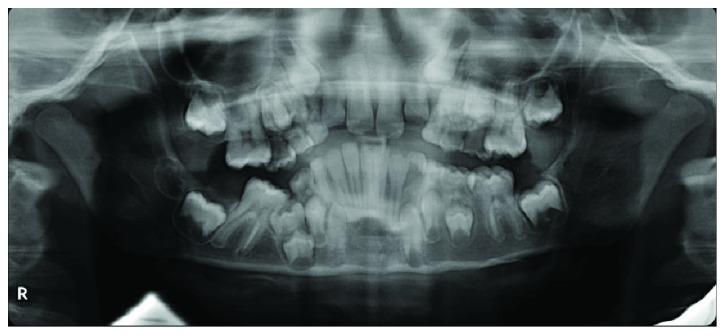

轻松实现间隙恢复:一例严重低位阻生乳磨牙病例

Space Regaining Made Easy: The Case of a Severely Infraoccluded Primary Molar.

Infraocclusion of deciduous molars is a quite common but challenging clinical situation that a paediatric dentist has to face in his everyday practice. This anomaly can lead to space loss, eruption disturbances of the permanent successor, and deformation of the occlusal plane. A case of a severely infraoccluded primary molar is presented. The treatment was carried out using a compressed NiTi wire applied only to the adjacent teeth. In three months, the space was recovered, and the infraoccluded temporary molar was extracted. After one year, the permanent successor erupted without any complication. The technique presented can be considered minimally invasive, and it involves cost- and time-efficient mechanics.

摘要

乳牙低位咬合是儿科牙医在日常临床实践中经常遇到但颇具挑战性的情况。这种异常可能导致间隙丧失、恒牙胚萌出障碍以及咬合平面变形。本文介绍了一例严重低位咬合的乳牙病例。治疗采用仅应用于相邻牙齿的压缩镍钛丝。三个月后,间隙恢复,低位咬合的乳牙被拔除。一年后,恒牙顺利萌出,未出现任何并发症。所介绍的技术可被视为微创技术,且具有成本效益高和省时的特点。